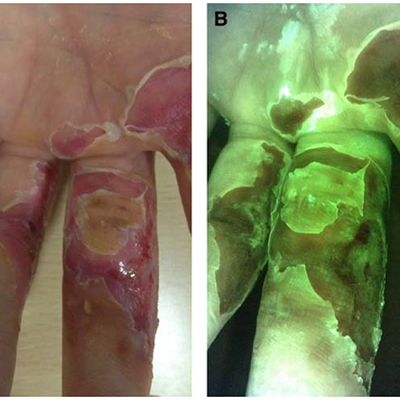

Skin Pigmentation Impacts the Clinical Diagnosis of Wound Infection: Imaging of Bacterial Burden to Overcome Diagnostic Limitations

Johnson J. et al. JREHD 2023

Bacterial Fluorescence Imaging to Address Racial Inequities in Wound Infection Assessment

Andersen, CA et al. Adv Skin & Wound Care 2024